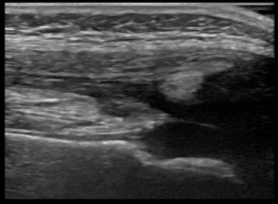

関節超音波検査は被曝がなくベッドサイドで実施できる有用なツールです。本研究では、一般診療に携わる小児科医や整形外科医に対して関節超音波検査の系統的な教育を行い、四肢痛を訴える小児に対する診療がどのように変化するかを教育前後で比較で評価します。これにより診断精度や治療方針の改善に寄与することを目指します。

幼児の膝関節超音波画像-